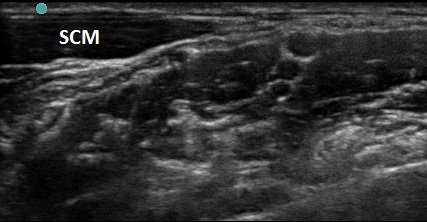

Figure 1. Transverse view over the sternocleidomastoid

- Use a high-frequency 8-12 MHz linear probe and begin scanning transversely over the anterior neck at the level of the cricoid. (Figure 1)

- Probe indicator oriented to operator’s left.

- Depth should be set between 4-8 cm, depending on the size of the patient’s neck.

- Trachea should be clearly seen as a midline hyperechoic arc.

- Slide the probe laterally to the lateral border of the sternocleidomastoid (SCM) (Figure 1), which is a thin muscle superficial to the carotid and jugular.